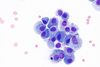

Macrophage

Platelet aggregation